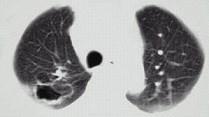

问题 21岁,近2个月来咳嗽,痰中带血丝,午后手心足底发热,盗汗、心悸,胸部CT见图,最可能的诊断是 ( )

选项 A.右上肺癌性空洞形成 B.继发性肺结核空洞形成 C.右肺脓肿 D.右上肺炎 E.肺囊肿

答案 B